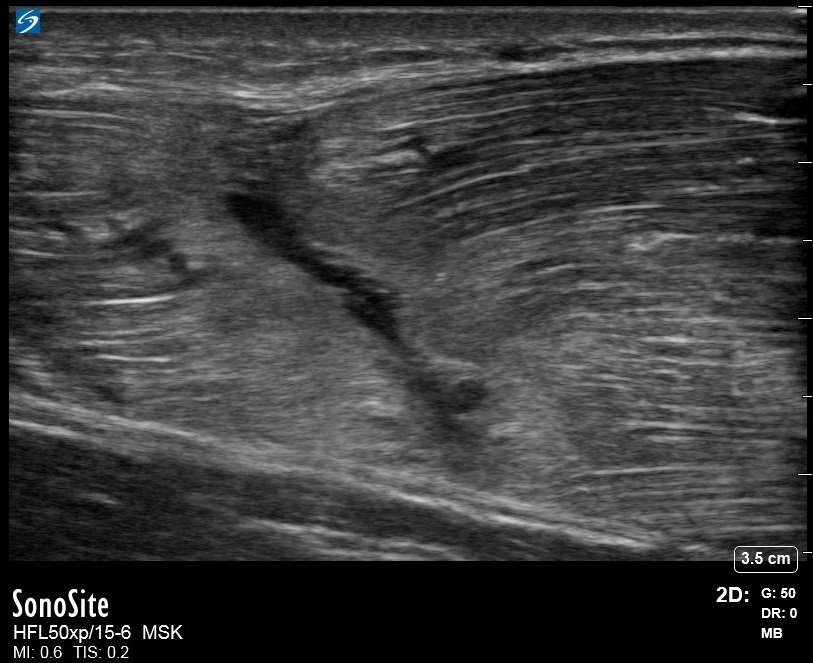

肩の引き裂かれた上腕三頭筋筋肉画像